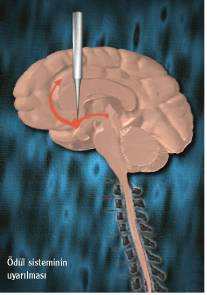

Ödüllendirme merkezi, hayvanlar­la yapılan deneyler sırasında keşfedil­di. Accumbens çekirdeklerine elek­trot yerleştirilen sıçanlar bir düğme­ye bastıklarında, çekirdeğe küçük miktarda elektriksel uyarılar gönde­riliyordu. Bu küçük uyarıyla kendisi­ni iyi hisseden hayvan, düğmeye bas­maya devam etmişti. Aynı elektrot ac­cumbens çekirdeğinden çıkarılıp ya­kınlarında bir bölgeye yerleştirildi-ğindeyse sıçanın düğmeye basmak­tan vazgeçtiği gözlenmişti. Çünkü, artık düğmeye bastığında keyif alamı­yordu.

Dopaminin bu süreçteki önemini anlamak için, aynı deney sırasında elektrot yine accumbens çekirdeğine yerleştirildi, ancak bu sefer dopamin salgılanması çeflitli ilaçlarla engellen­di. Hayvan, accumbens çekirdeği uyarıldığı halde dopamin salımı ilaç­larla engellendiğinden, düğmeye bas­maktan vazgeçti.